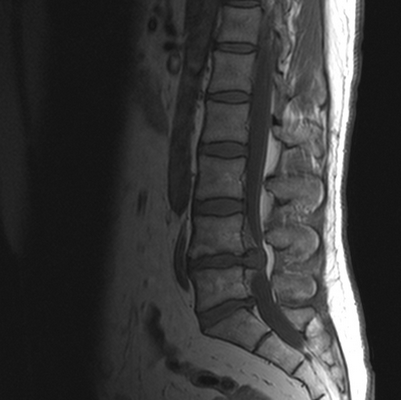

Грыжа диска между телами 4 и 5 поясничных позвонков на МРТ

Гигантская грыжа поясничного отдела позвоночника на МРТ